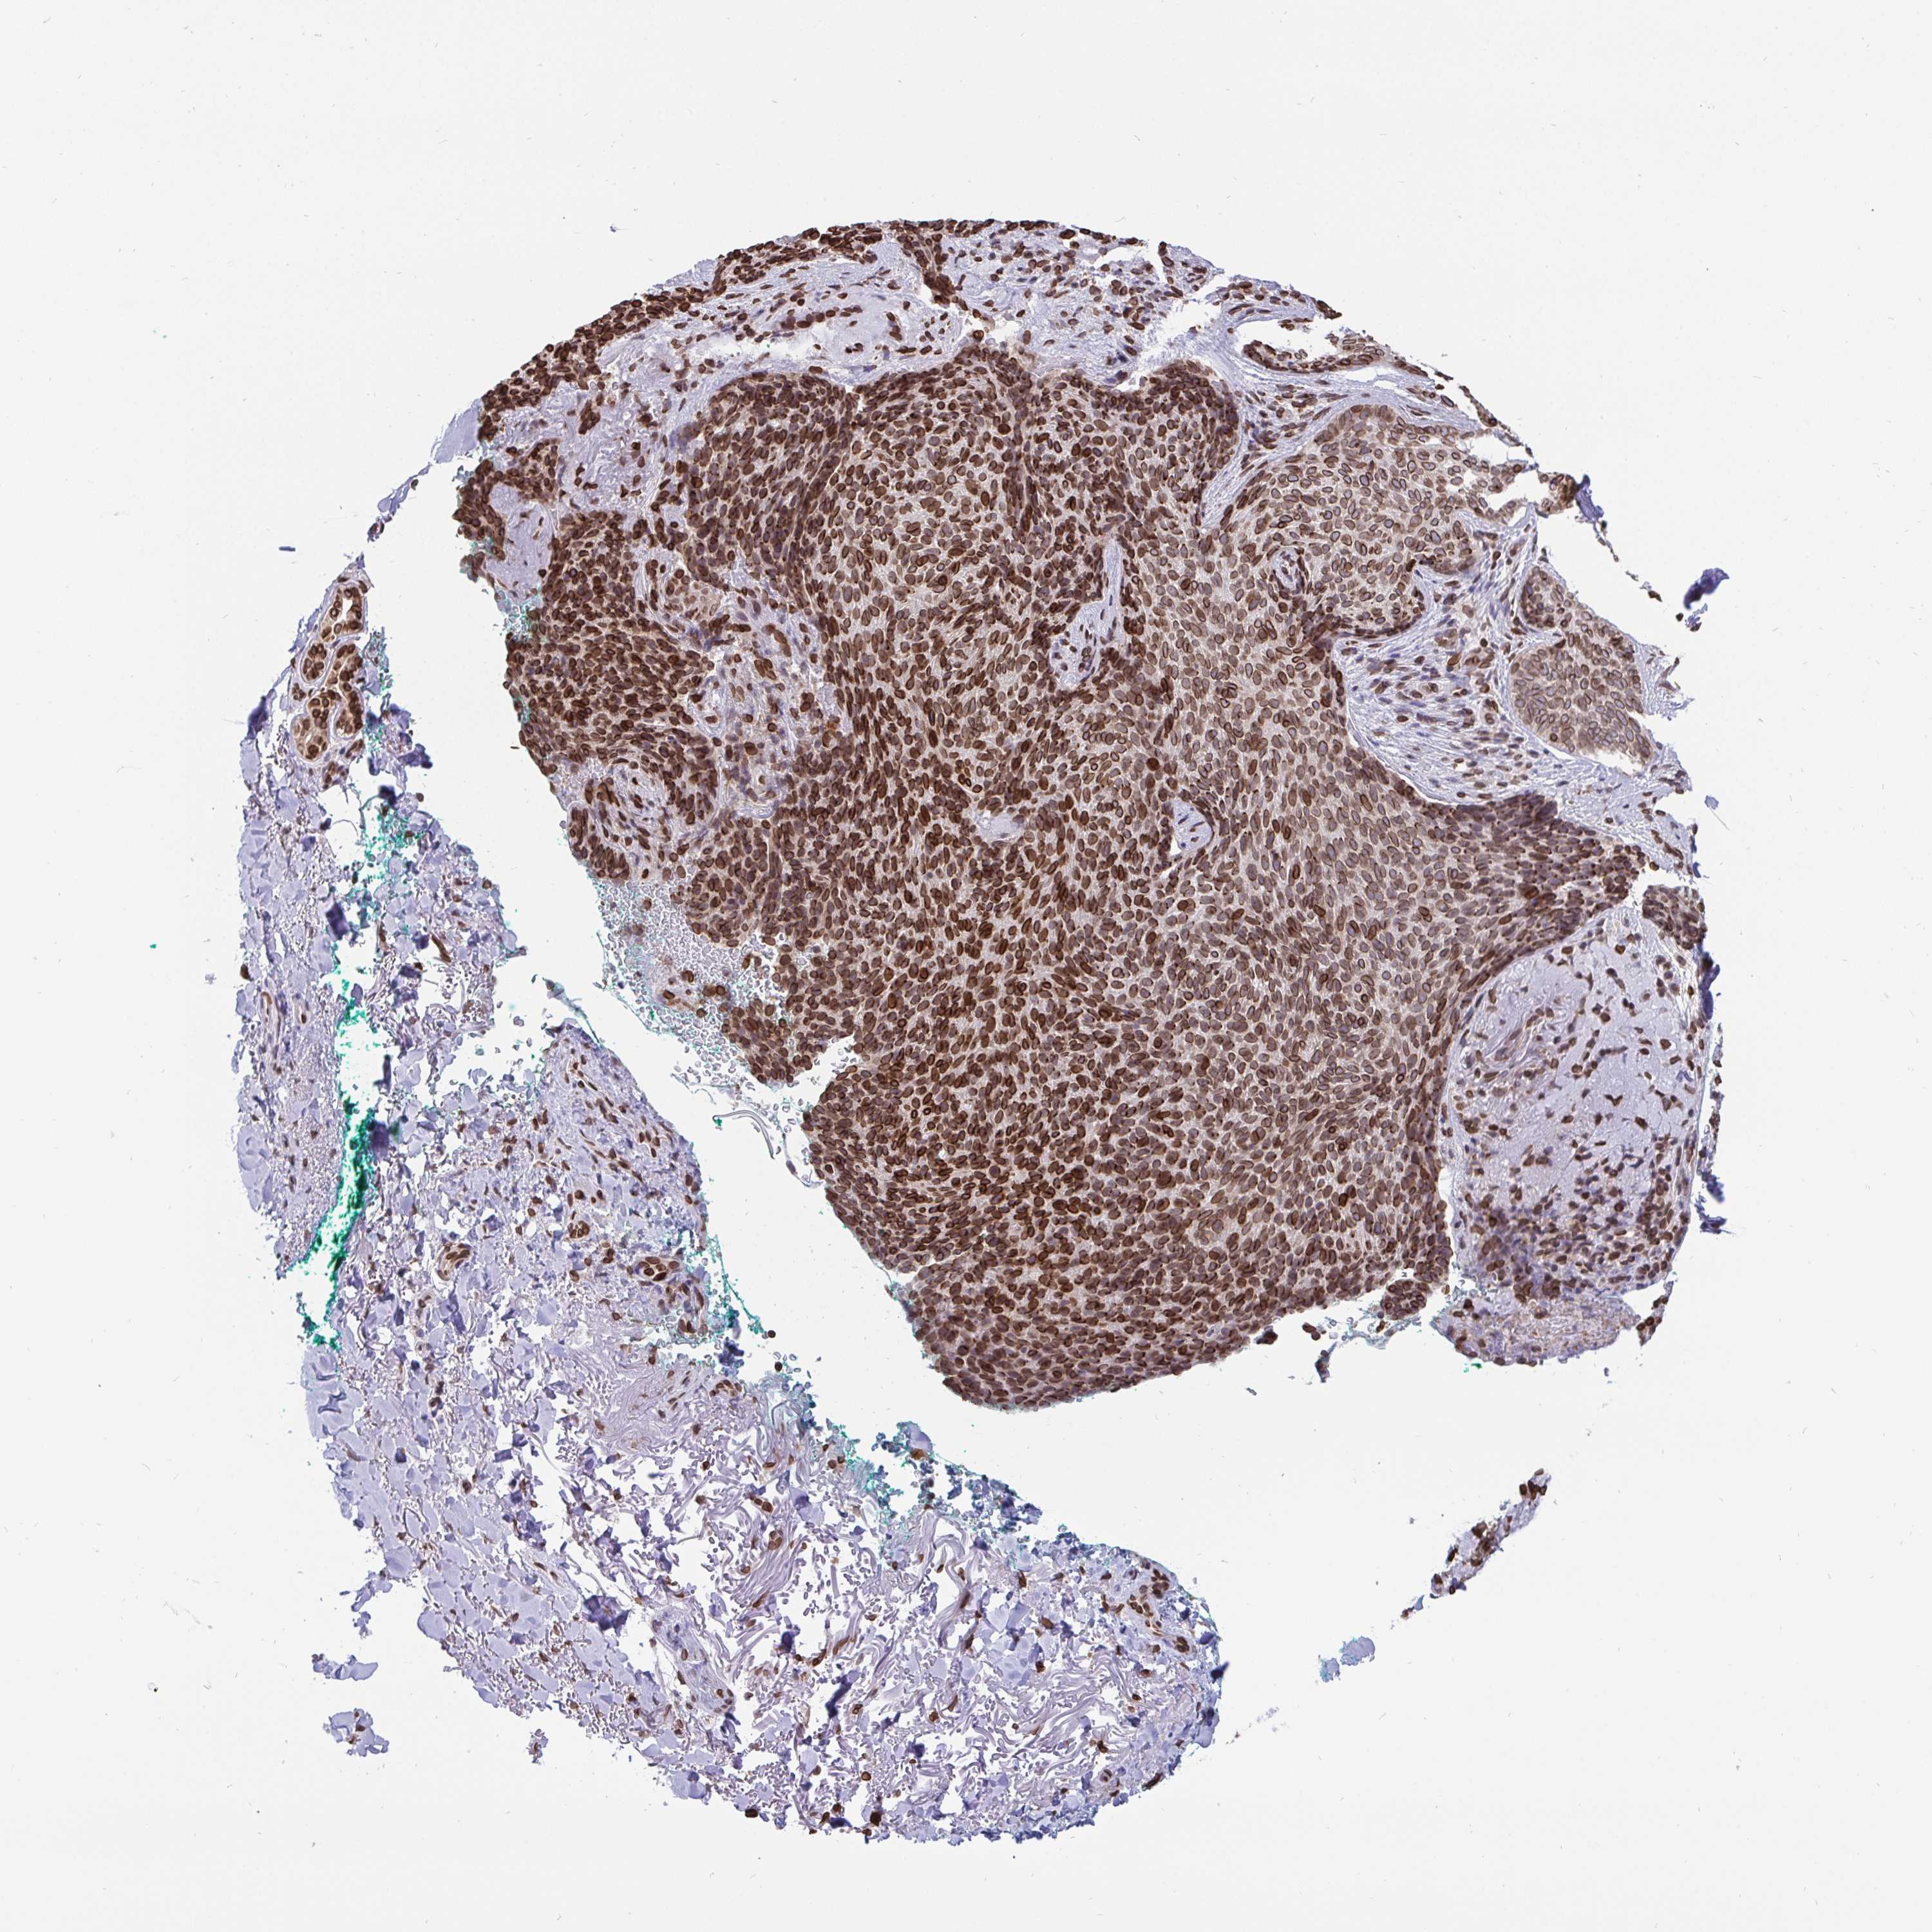

SKIN CANCER - Protein expressioni

A mouse-over function shows sample information and annotation data. Click on an image to view it in a full screen mode. Samples can be filtered based on level of antibody staining by selecting one or several of the following categories: high, medium, low and not detected. The assay and annotation is described here.

Antibody staining in the annotated cell types in the current human tissue is reported as not detected, low, medium, or high, based on conventional immunohistochemistry profiling in selected tissues. This score is based on the combination of the staining intensity and fraction of stained cells.

Each image is clickable and will lead to virtual microscopy that enables deeper exploration of all samples and also displays staining intensity scores, fraction scores and subcellular localization as well as patient and tissue information for each sample.

Antibody CAB002029

Basal cell carcinoma

Squamous cell carcinoma, NOS